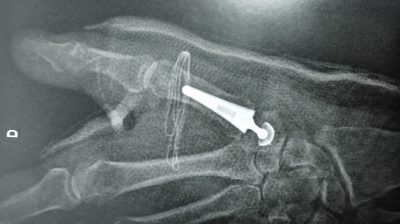

1er Prothèse pour arthrose du pouce à la Clinique Saint Charles

L’arthrose du pouce touche chaque année de plus en plus de femmes et d’hommes. Plus actifs dans leurs vies quotidiennes, cette arthrose devient ...